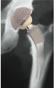

| Preoperative templating |

High neck resection |

Rasping the femur |

| Omni ARCTM stem |

The new Omni ARCTM stem looks like it may have substantial promise as an alternative to both HR and traditional THA. It’s design as a tissue sparing implant with proximal loading to prevent bone loss may prove to have substantial benefits in the future.